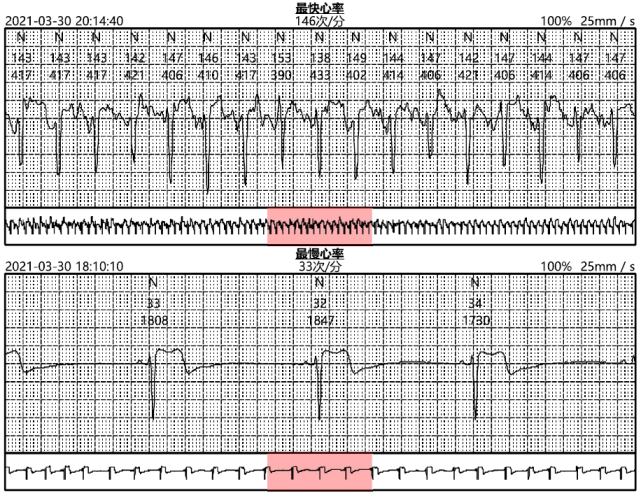

2,房性早搏15次;平均心率为65次/分,最快心率是146次/分,发生于2021